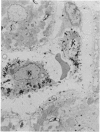

Polymeric myeloma IgA, labelled with 125I, was injected intravenously into rats that were killed 5, 30, or 60 min later and the livers removed, fixed and sectioned. Autoradiographs of ultra-thin sections examined in the electron microscope showed that the IgA first became bound to the plasma membrane of the hepatocytes but after 30 min much of it was transported across their cytoplasm and became localized around the bile canaliculi. At this time, autoradiographs of 1 micrometer sections examined in the light microscope showed the contents of the bile ducts in the portal tracts to be labelled heavily. These results confirm the previous finding of rapid transport of IgA across the liver and show directly that the hepatocytes are the cells that carry it out. No intracellular organelle or vesicular structure, discernible within the resolving power of the techniques used, could be implicated in the transport mechanism.